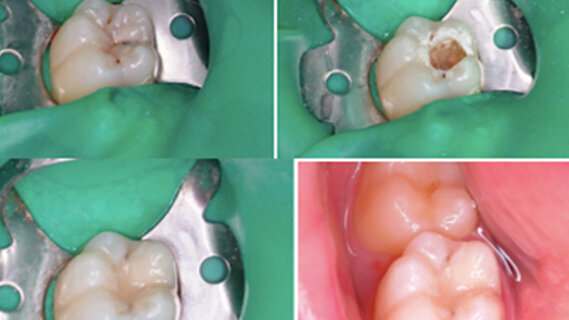

Patrizia est une enfant de 12 ans présentant un déficit intellectuel : elle acceptait très mal l’anesthésie locale, ce qui limitait la possibilité de la traiter. Une visite de contrôle de la patiente a révélé une carie sur la dent 46 et nous avons pris le risque d’une approche par laser Er:YAG pour traiter cette carie profonde, en appliquant la méthode dite du « Tell-Show-Do » (expliquer, montrer, faire) sans anesthésie locale. Nous avons obtenu une excellente coopération de la patiente et la possibilité de réaliser une restauration de qualité. Grâce aussi à l’excellente coopération, nous avons pu mettre en place une digue en caoutchouc. Nous avons utilisé le laser Er:YAG en mode SSP (Super Short Pulse), énergie de 250 mJ, fréquence de 10 Hz, pièce à main à miroir pour une intervention sans contact (fluence : 39,3 J/cm2) et spray eau/air (Fig. 1).